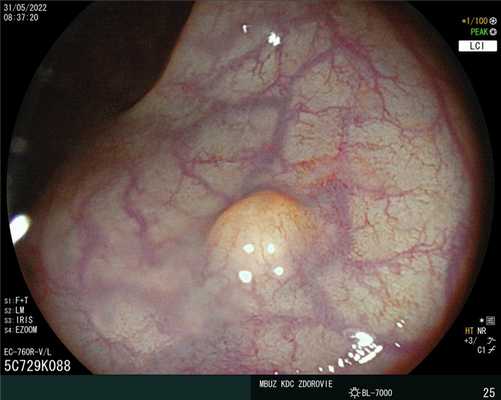

Нейроэндокринная опухоль G1